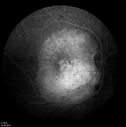

Choroidal Metastases - Both Eyes - Exudative Retinal Detachmentvu 1412 fois58-year-old man smoke a pack of cigarettes a day. He has had some ribcage pain for about the last two weeks. He also had a sinus infection for about two weeks, and he has also had hazy vision on the superior visual field in the left eye for about the last two weeks. vision is 20/25 in both eyes

Choroidal Metastases - Both Eyes - Exudative Retinal Detachmentvu 907 fois58-year-old man smoke a pack of cigarettes a day. He has had some ribcage pain for about the last two weeks. He also had a sinus infection for about two weeks, and he has also had hazy vision on the superior visual field in the left eye for about the last two weeks. vision is 20/25 in both eyes

Choroidal Metastases - Both Eyes - Exudative Retinal Detachmentvu 823 fois58-year-old man smoke a pack of cigarettes a day. He has had some ribcage pain for about the last two weeks. He also had a sinus infection for about two weeks, and he has also had hazy vision on the superior visual field in the left eye for about the last two weeks. vision is 20/25 in both eyes

Choroidal Metastases - Both Eyes - Exudative Retinal Detachmentvu 796 fois58-year-old man smoke a pack of cigarettes a day. He has had some ribcage pain for about the last two weeks. He also had a sinus infection for about two weeks, and he has also had hazy vision on the superior visual field in the left eye for about the last two weeks. vision is 20/25 in both eyes